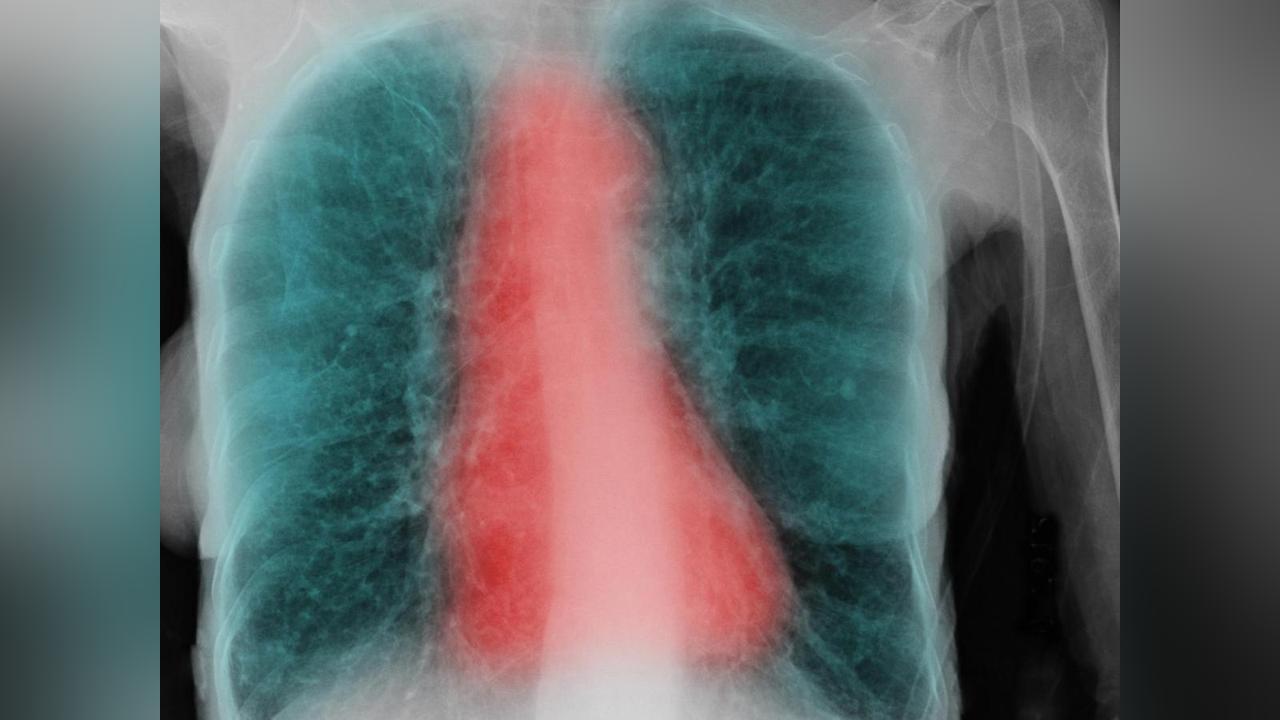

Ces scans des voies aériennes (en rouge) et des poumons (en noir) montrent le spectre de la dysanapsie, avec des voies aériennes plus petites en proportion de la taille des poumons (gauche) par rapport aux voies aériennes de taille normale (milieu), et plus grandes que les voies aériennes normales (droite). Cliquez pour voir en plus grand. Crédit: VIDA Apollo Software, courtesy of Eric A. Hoffman, PhD, Radiology, University of Iowa Carver College of Medicine.